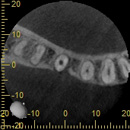

歯科用コーンビームCTの特徴

歯・歯周組織や病変の3次元的描出

通常、歯科で用いるレントゲンは、1方向から投影した画像で診断するため、歯や歯周組織・病変などの立体的な把握が困難です。

しかし、CTを用いることで、従来のエックス線画像のみでは原因が特定できなかった病変を描出し、診断することが可能となりました。

インプラントへの応用

インプラント治療において、CTによる術前診断は不可欠のものとなっています。

CT画像上で、インプラントを埋入する部位の骨の幅・厚み・形態・骨質、さらには上顎洞や血管・神経との距離、上部構造の方向との関連性などを総合的に把握することにより、安全で確実な治療が可能となります。

逆に言うならば、CTによる術前診断なしのインプラント治療は危険と言わざるを得ません。さらには、術後の埋入状態や経過観察時のCT撮影が行われるならば、それに越したことはありません。

当院では、インプラント治療時には、歯科用コーンビームCT「KR―XSCAN」㈱)近畿レントゲン工業社を用いて、術前、術後および経過観察時のCT撮影を行っています。